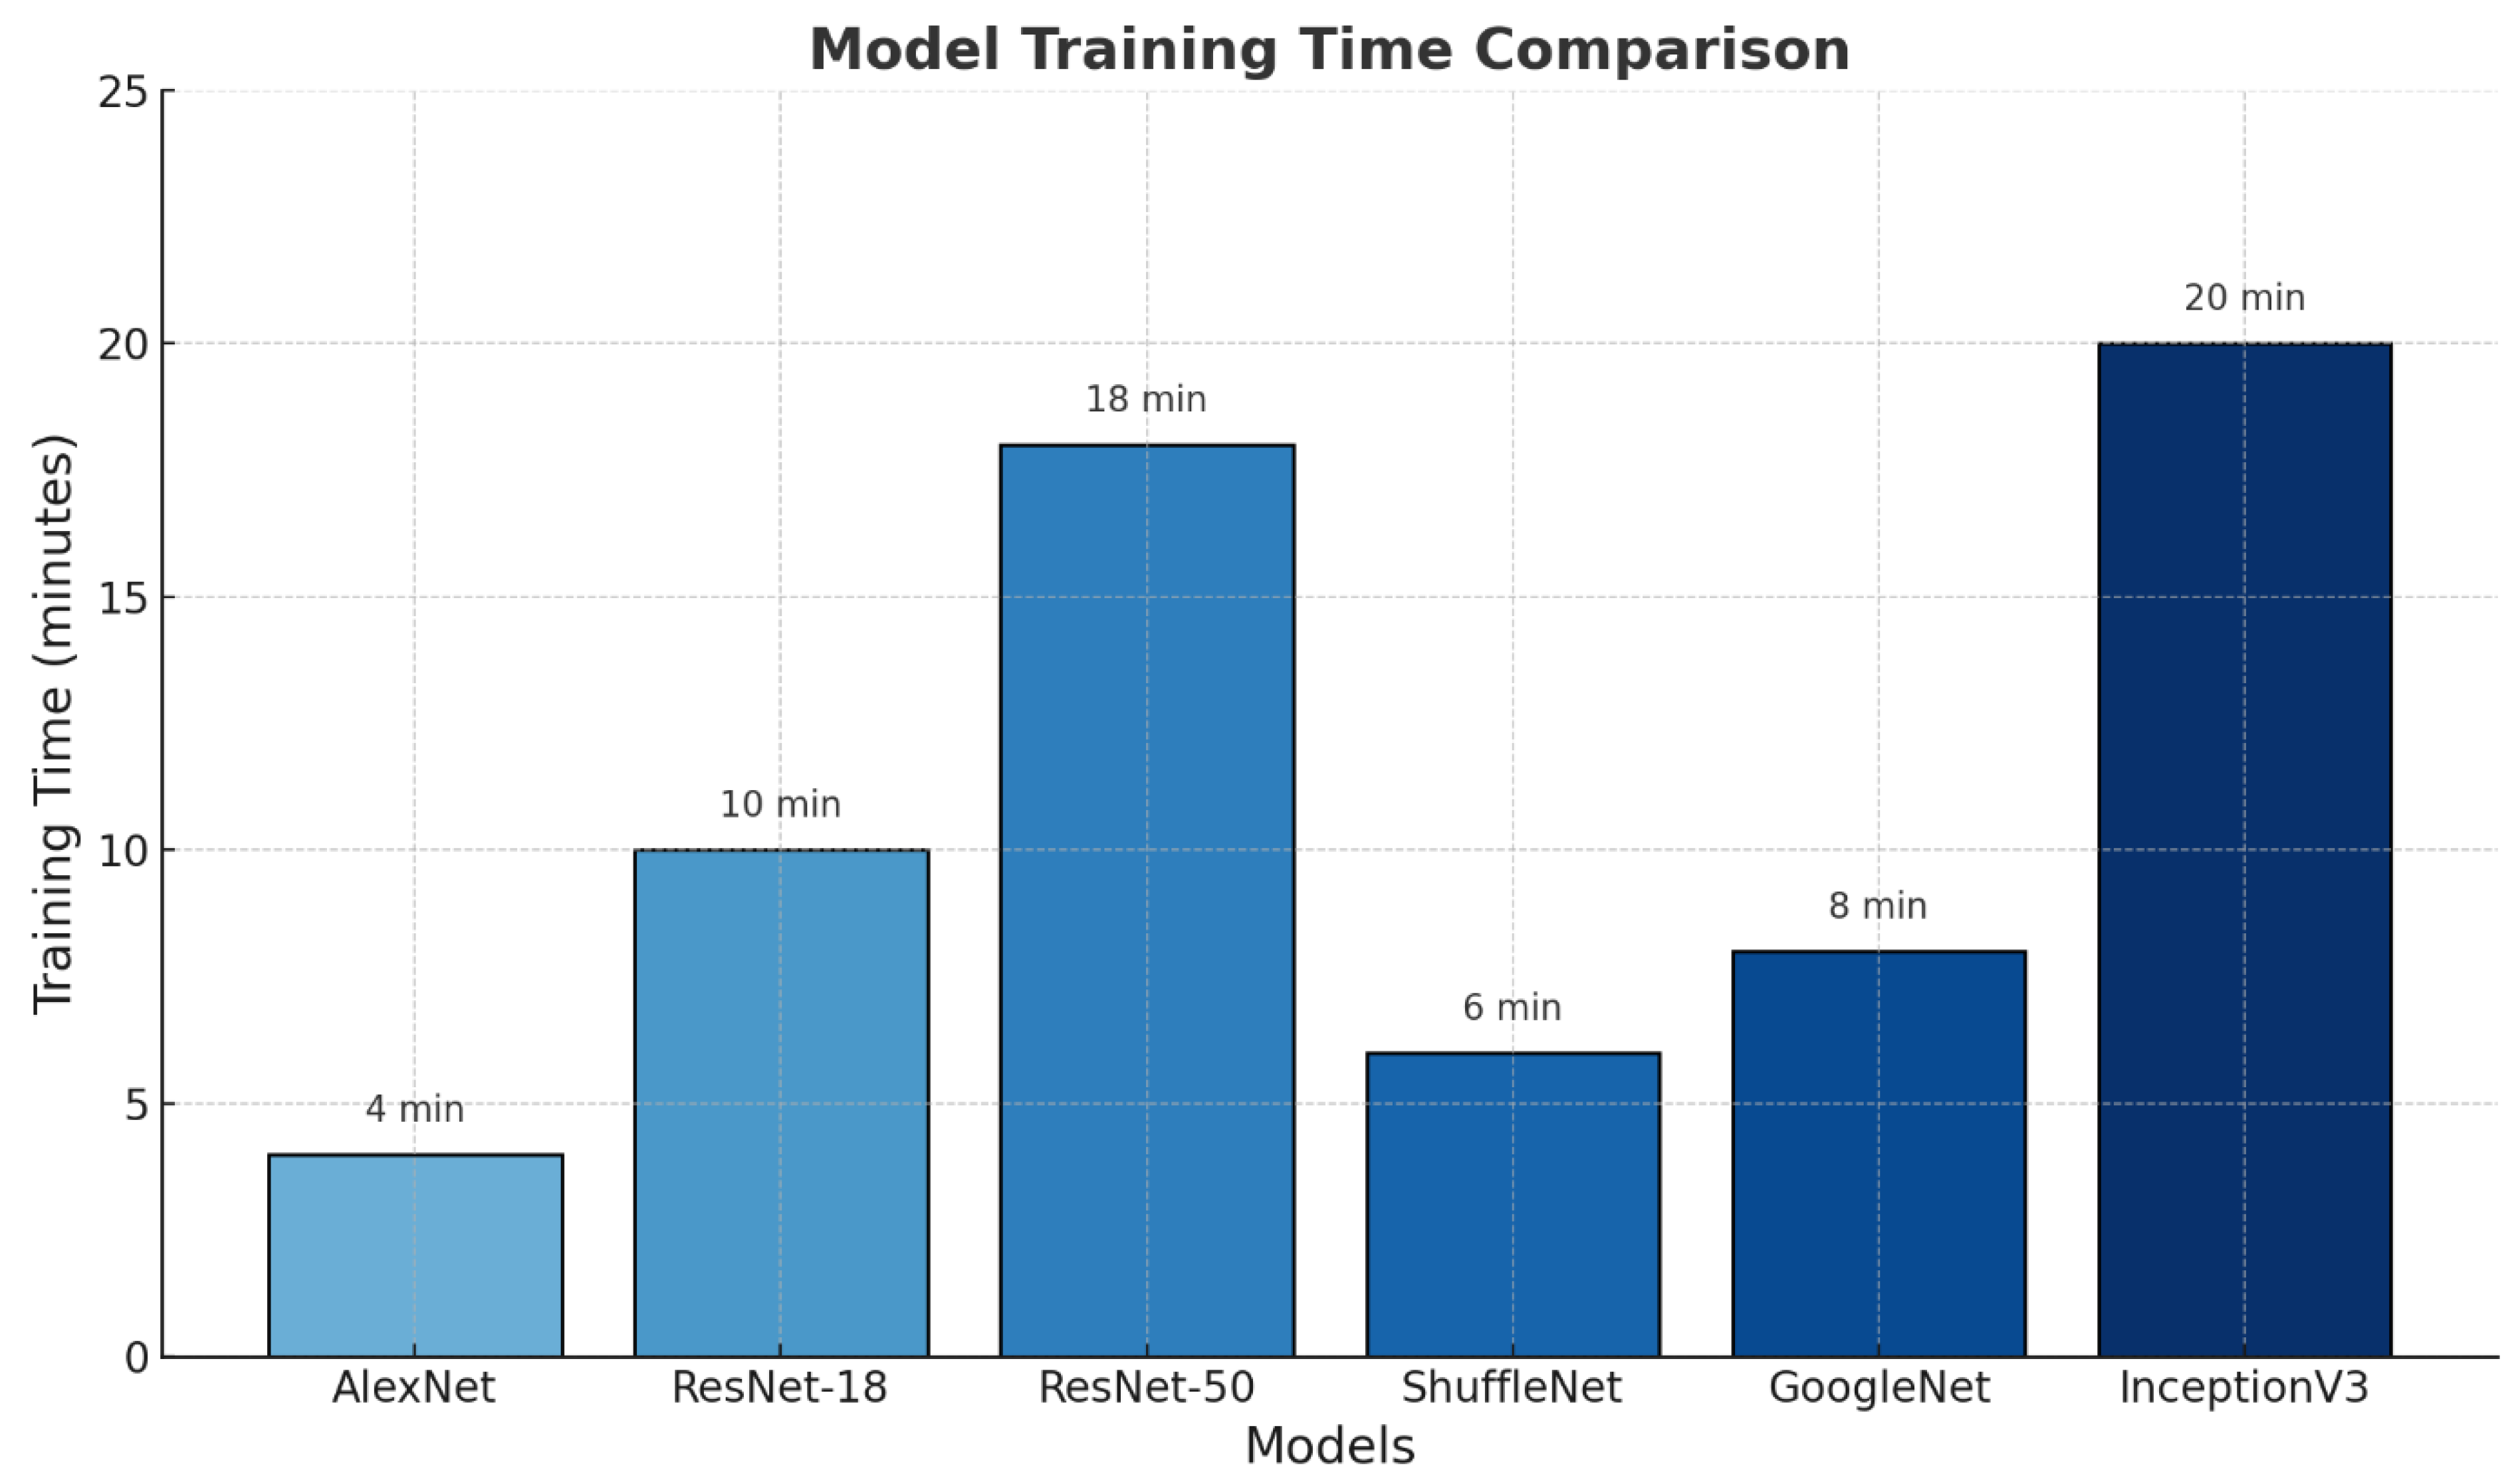

Figure 6 shows the training times of the different deep learning models used in this study.

The AlexNet model had the shortest training time (4 min), whereas the InceptionV3 model had the longest training time (20 min). This is directly proportional to the architectural complexity and number of layers in the models. Simpler architectures are trained in shorter periods, whereas deeper and more complex structures require longer training periods.